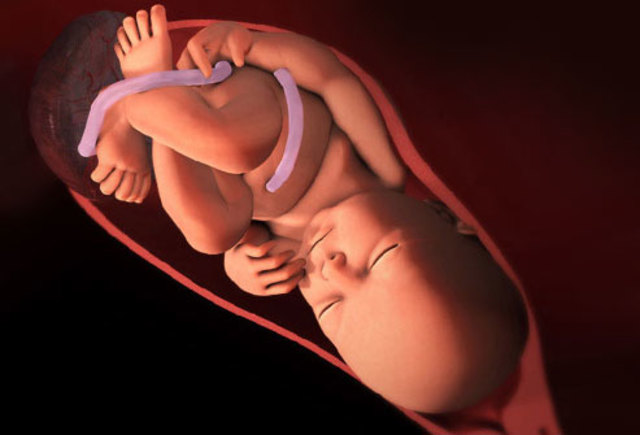

• Week Thirty-Six Progression

Week Thirty-Six Progression

The baby is about 19 inches in size and weighs around 2.7 kg.They are continuously gaining fat and around this week they might drop into the birth canal.

• Week Thirty-Seven Progression

Week Thirty-Seven Progression

At this stage the baby is gaining one ounce per day and it is possible that their mother's water can break at anytime.